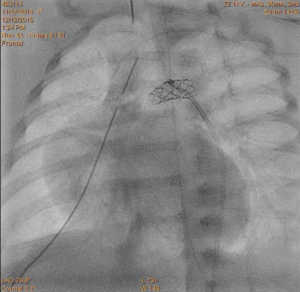

Noworodek z zarośnięciem zastawki płucnej bez ubytku przegrody międzykomorowej i hipoplazją prawej komory serca;

A – pomiary średnicy przewodu tętniczego w aortografii;

B – stan po implantacji stentu do przewodu tętniczego.